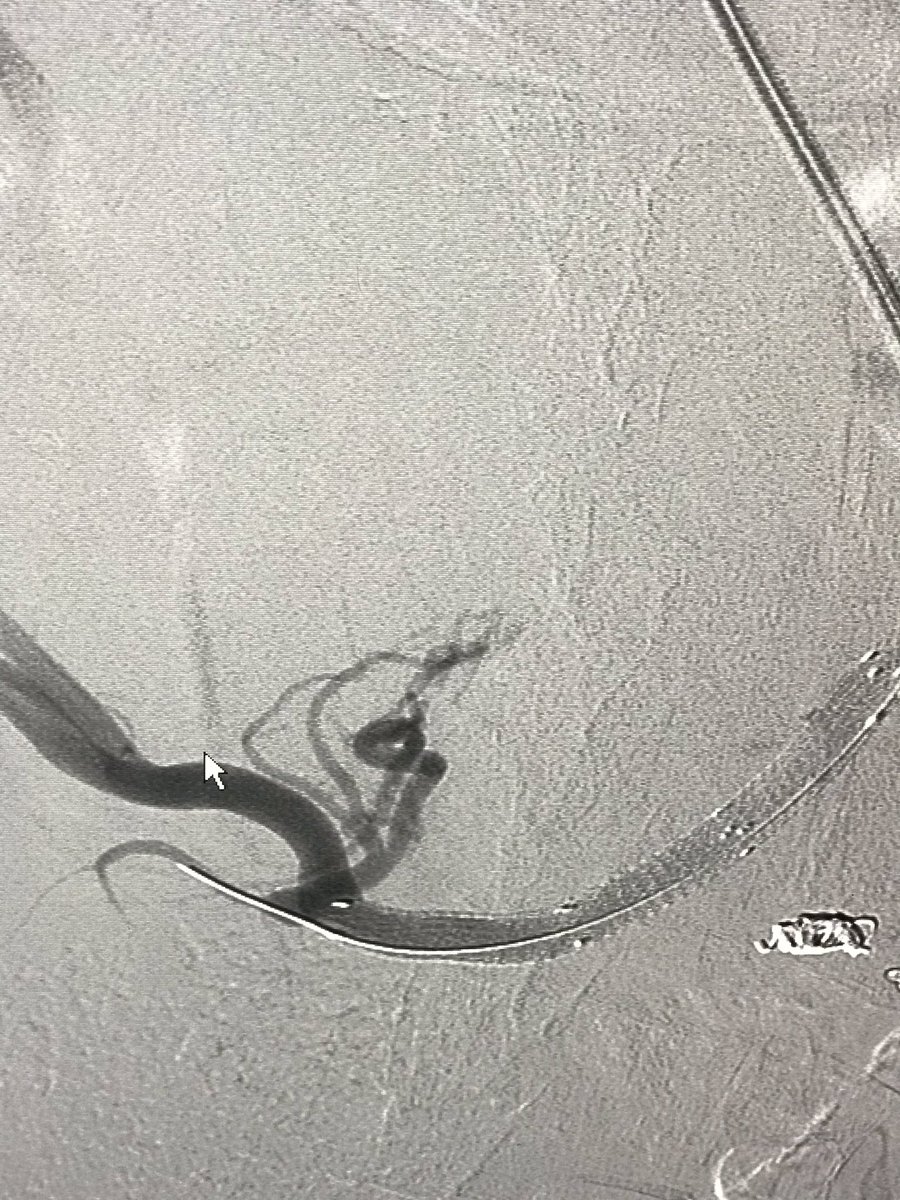

Transradial n-BCA Glue Embolization of Giant Pelvic Arteriovenous Malfor... youtu.be/BlGp9gZV6wk via @YouTube